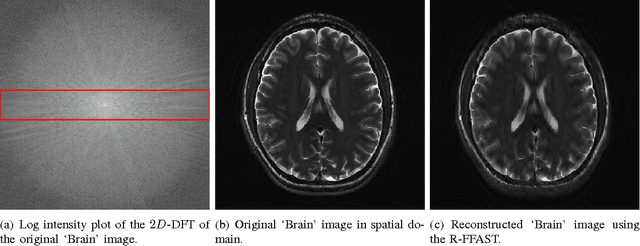

The Fast Fourier Transform (FFT) is the most efficiently known way to compute the Discrete Fourier Transform (DFT) of an arbitrary n-length signal, and has a computational complexity of O(n log n). If the DFT X of the signal x has only k non-zero coefficients (where k < n), can we do better? In [1], we addressed this question and presented a novel FFAST (Fast Fourier Aliasing-based Sparse Transform) algorithm that cleverly induces sparse graph alias codes in the DFT domain, via a Chinese-Remainder-Theorem (CRT)-guided sub-sampling operation of the time-domain samples. The resulting sparse graph alias codes are then exploited to devise a fast and iterative onion-peeling style decoder that computes an n length DFT of a signal using only O(k) time-domain samples and O(klog k) computations. The FFAST algorithm is applicable whenever k is sub-linear in n (i.e. k = o(n)), but is obviously most attractive when k is much smaller than n. In this paper, we adapt the FFAST framework of [1] to the case where the time-domain samples are corrupted by a white Gaussian noise. In particular, we show that the extended noise robust algorithm R-FFAST computes an n-length k-sparse DFT X using O(klog ^3 n) noise-corrupted time-domain samples, in O(klog^4n) computations, i.e., sub-linear time complexity. While our theoretical results are for signals with a uniformly random support of the non-zero DFT coefficients and additive white Gaussian noise, we provide simulation results which demonstrates that the R-FFAST algorithm performs well even for signals like MR images, that have an approximately sparse Fourier spectrum with a non-uniform support for the dominant DFT coefficients.